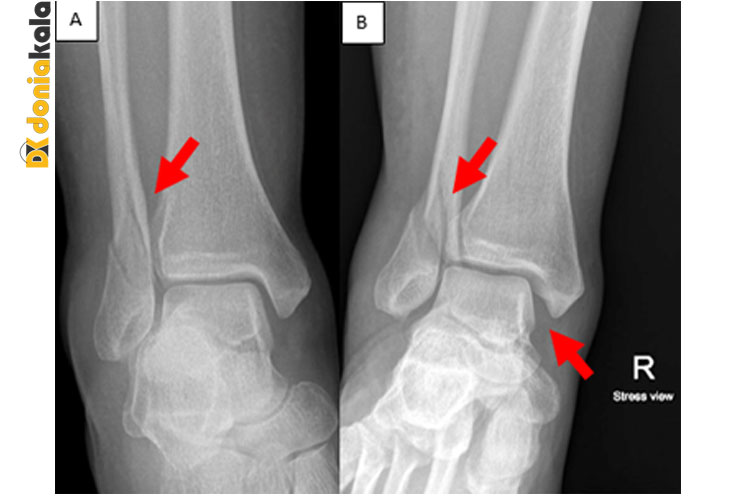

مچ پای شکسته: مچ پا شکسته یا شکستگی های متعدد یک یا چند استخوان از سه استخوان در مفصل مچ پا است: درشت نی (استخوان ساق پا)، نازک نی (استخوان خارجی ساق پا) و تالوس.

آناتومی اسکلتی مچ پا: رباط ها استخوان را به استخوان متصل می کنند تا ثبات مفاصل را فراهم کنند. آنها معمولاً در صورت پیچ خوردگی مچ پا آسیب می بینند. آنها همچنین می توانند در ارتباط با شکستگی مچ پا آسیب ببینند. هنگامی که رباط ها پاره می شوند و با شکستگی مچ پا همراه هستند، این آسیب می تواند مچ پا را ناپایدار کند. رباط دلتوئید در قسمت داخلی مچ پا قرار دارد و اکثریت ثبات مچ پا را تامین می کند. اگر رباط دلتوئید همراه با شکستگی پاره شود، مچ پا به طور کلی ناپایدار است. در مفصل مچ پا یا هر مفصلی در بدن، دو یا چند استخوان نسبت به یکدیگر حرکت می کنند. بین استخوان ها یک بالشتک یا آستر وجود دارد که به آن غضروف می گویند. نازک شدن یا آسیب دیدن این بالشتک می تواند منجر به آرتریت یا التهاب در مفصل شود.